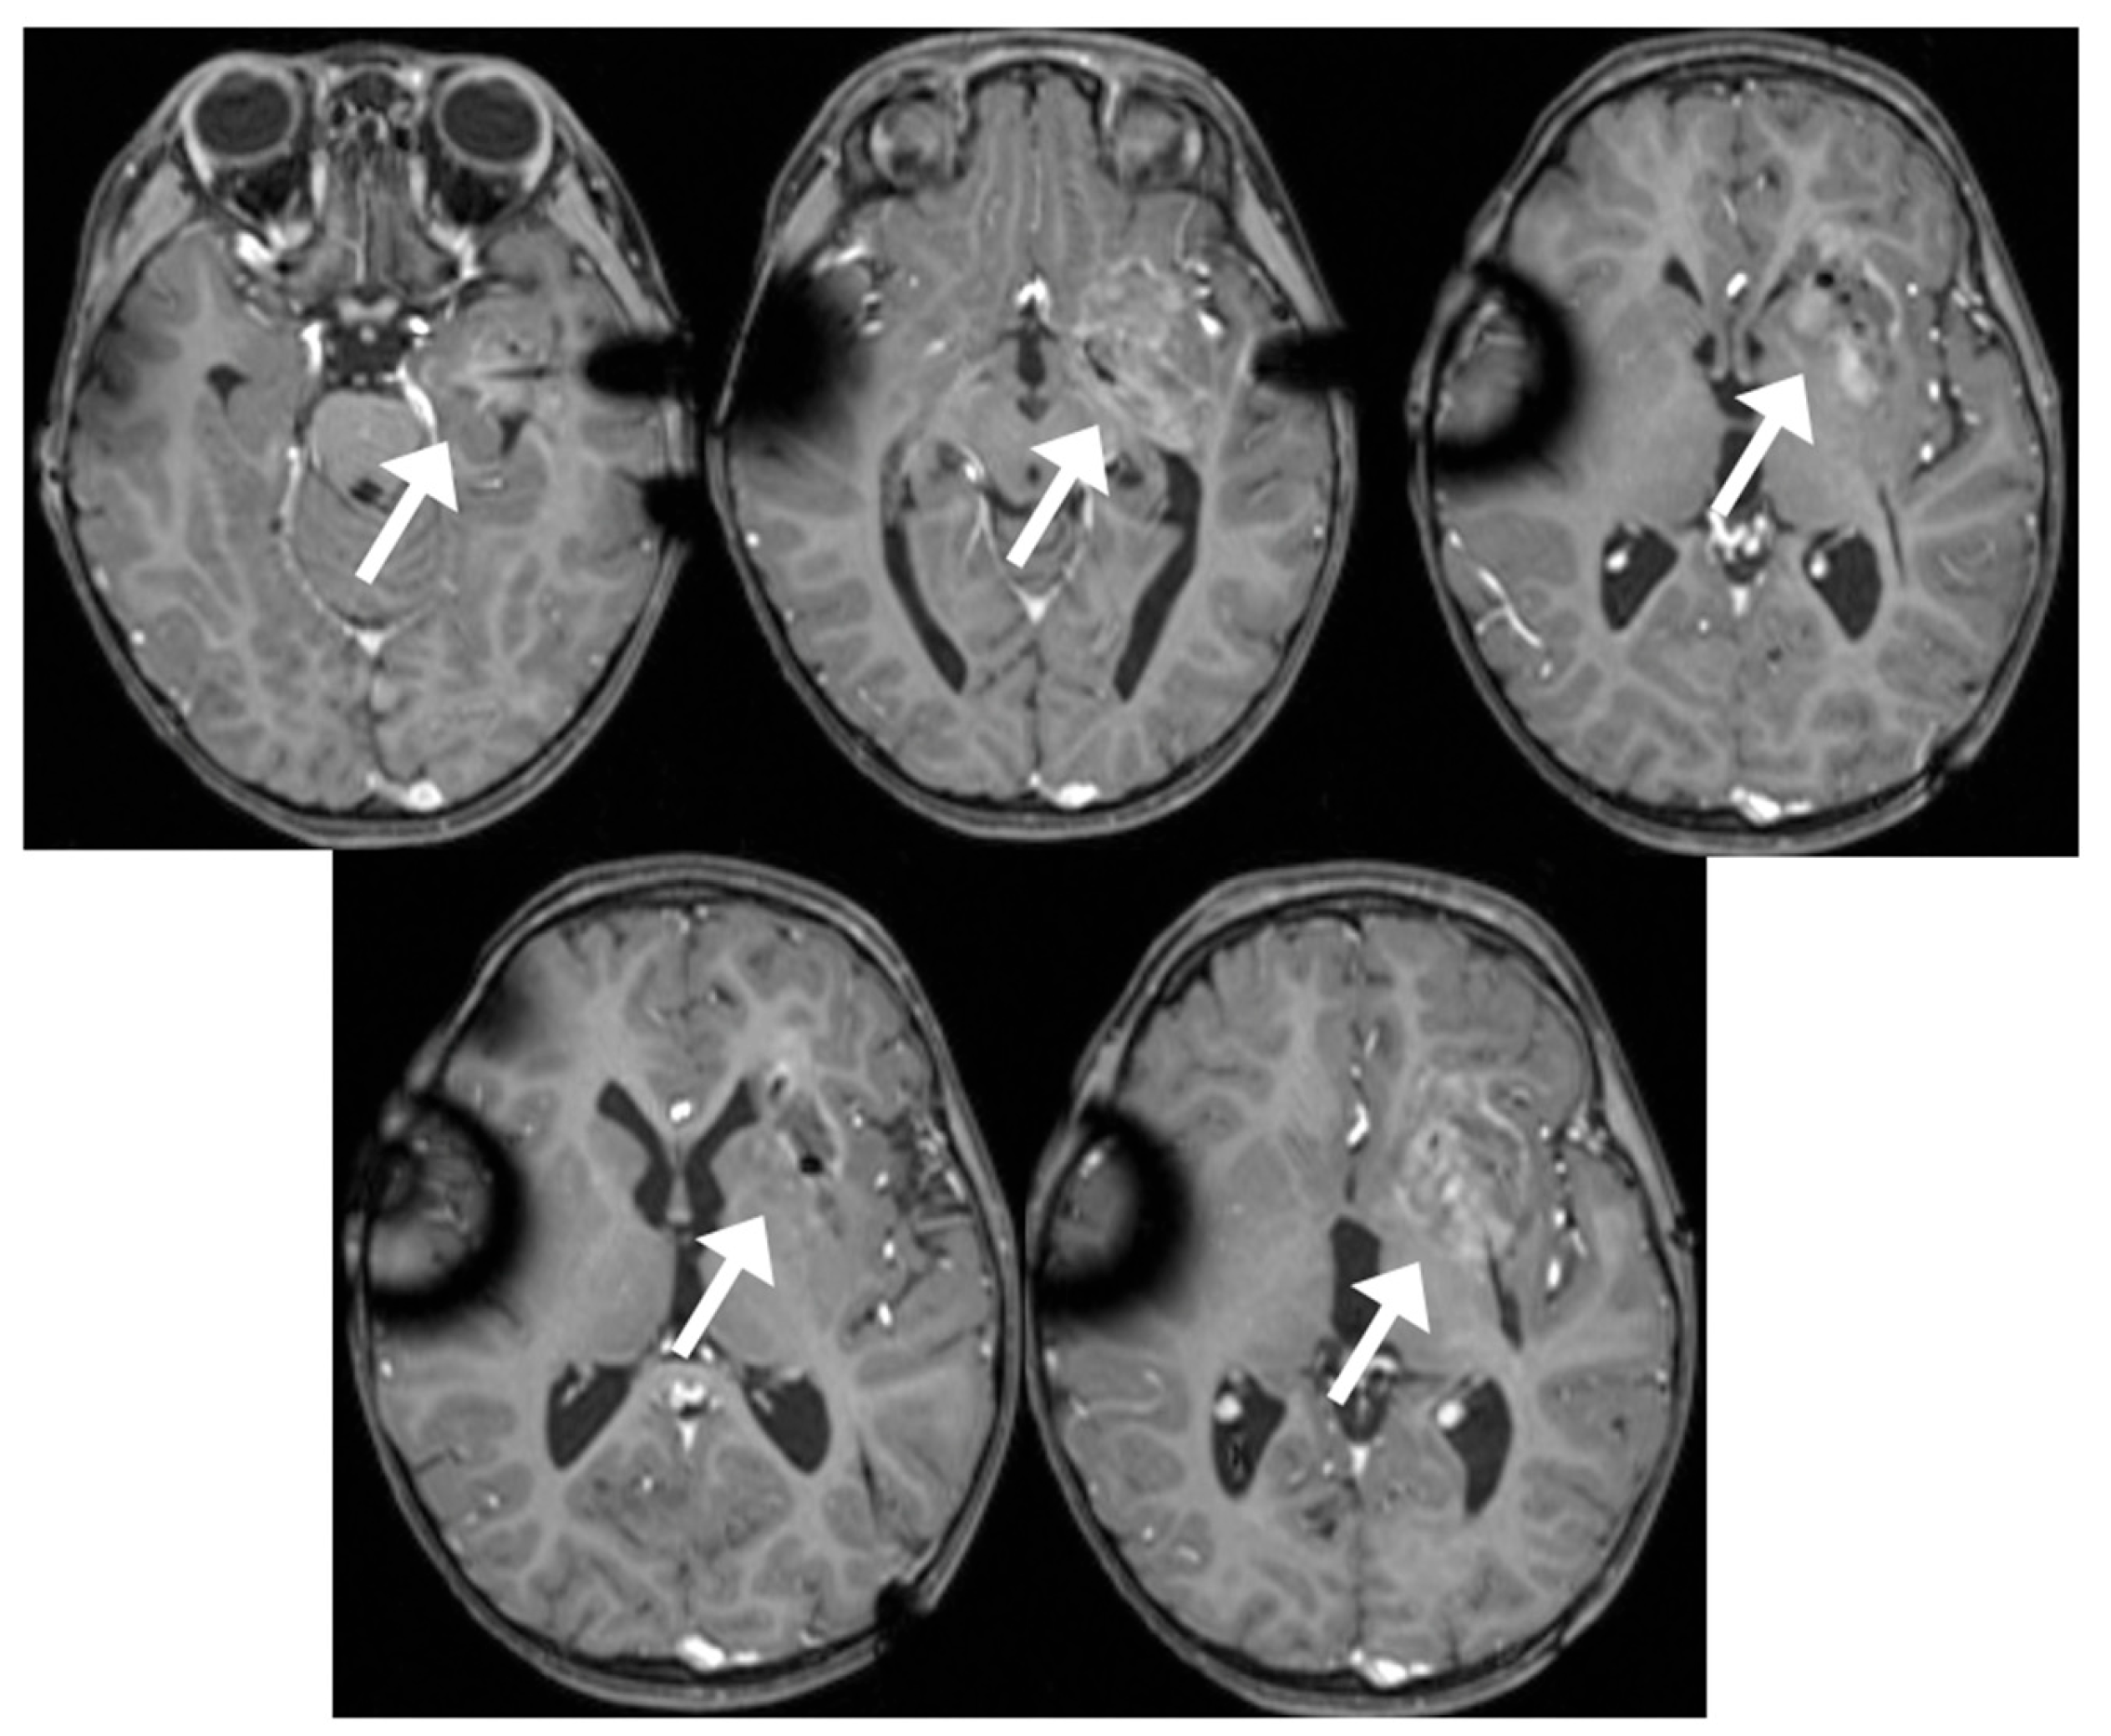

Case Report